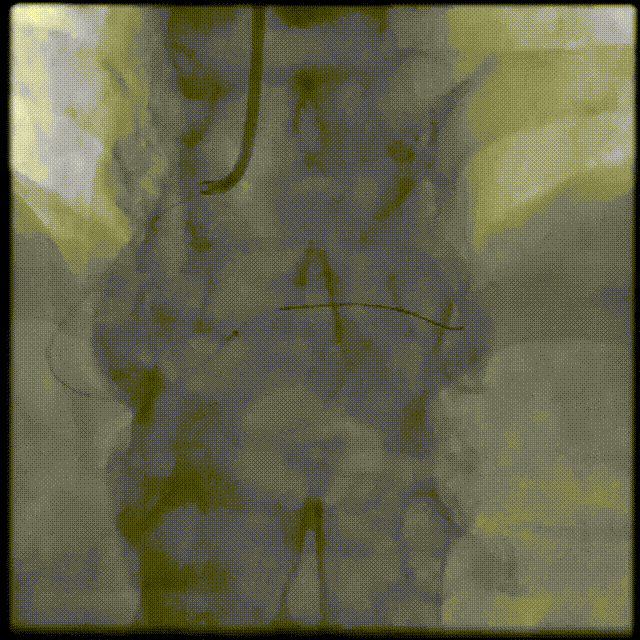

介入经过-第一次PCI旋支血运重建成功

介入经过-第二次PCI

RCA : 7F JL4 GC LCA : 6F JL4

FINECROSS MC + Pilot 50

介入经过-第二PCI

Sprinter1.25*6mm&2.5*15mm,2.5*35mm&2.5*15mm Stent

介入经过-最终造影